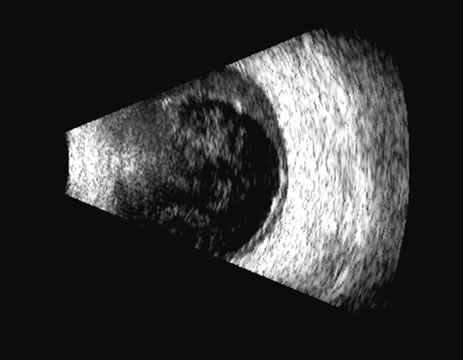

Fig. 23. A hemangioma of the posterior pole is usually very echoic, appearing solid on B-scan with little or no reduction in amplitude on A-scan between the retinal surface and the posterior tumor wall.

The differentiation of tumor tissues is made possible by differences in cellular organization and concentration.29 Acoustically, these are termed as differences in backscattering properties.30–32 A homogeneous solid tissue, such as the lens or the optic nerve, may present few or no echogenic discontinuities and thus appear anechoic and cyst-like. (An echogenic discontinuity is technically an acoustic impedance mismatch in which the acoustic impedance is the product of the density and the speed of sound in each tissue.) A fluid–smooth tissue boundary has a high mismatch or discontinuity and thus produces a high-amplitude echo. A hemangioma with alternating blood- and tissue-lined sacs thus produces a solid-appearing tissue with high-amplitude echoes seen at all depths of the tissue. A metastatic tumor is nearly always a very heterogeneous tissue with randomly organized clumps of similar cells bounded by strands of vessels, necrotic areas, and connective tissue, thus producing a pattern of moderately high-amplitude sustained echoes.